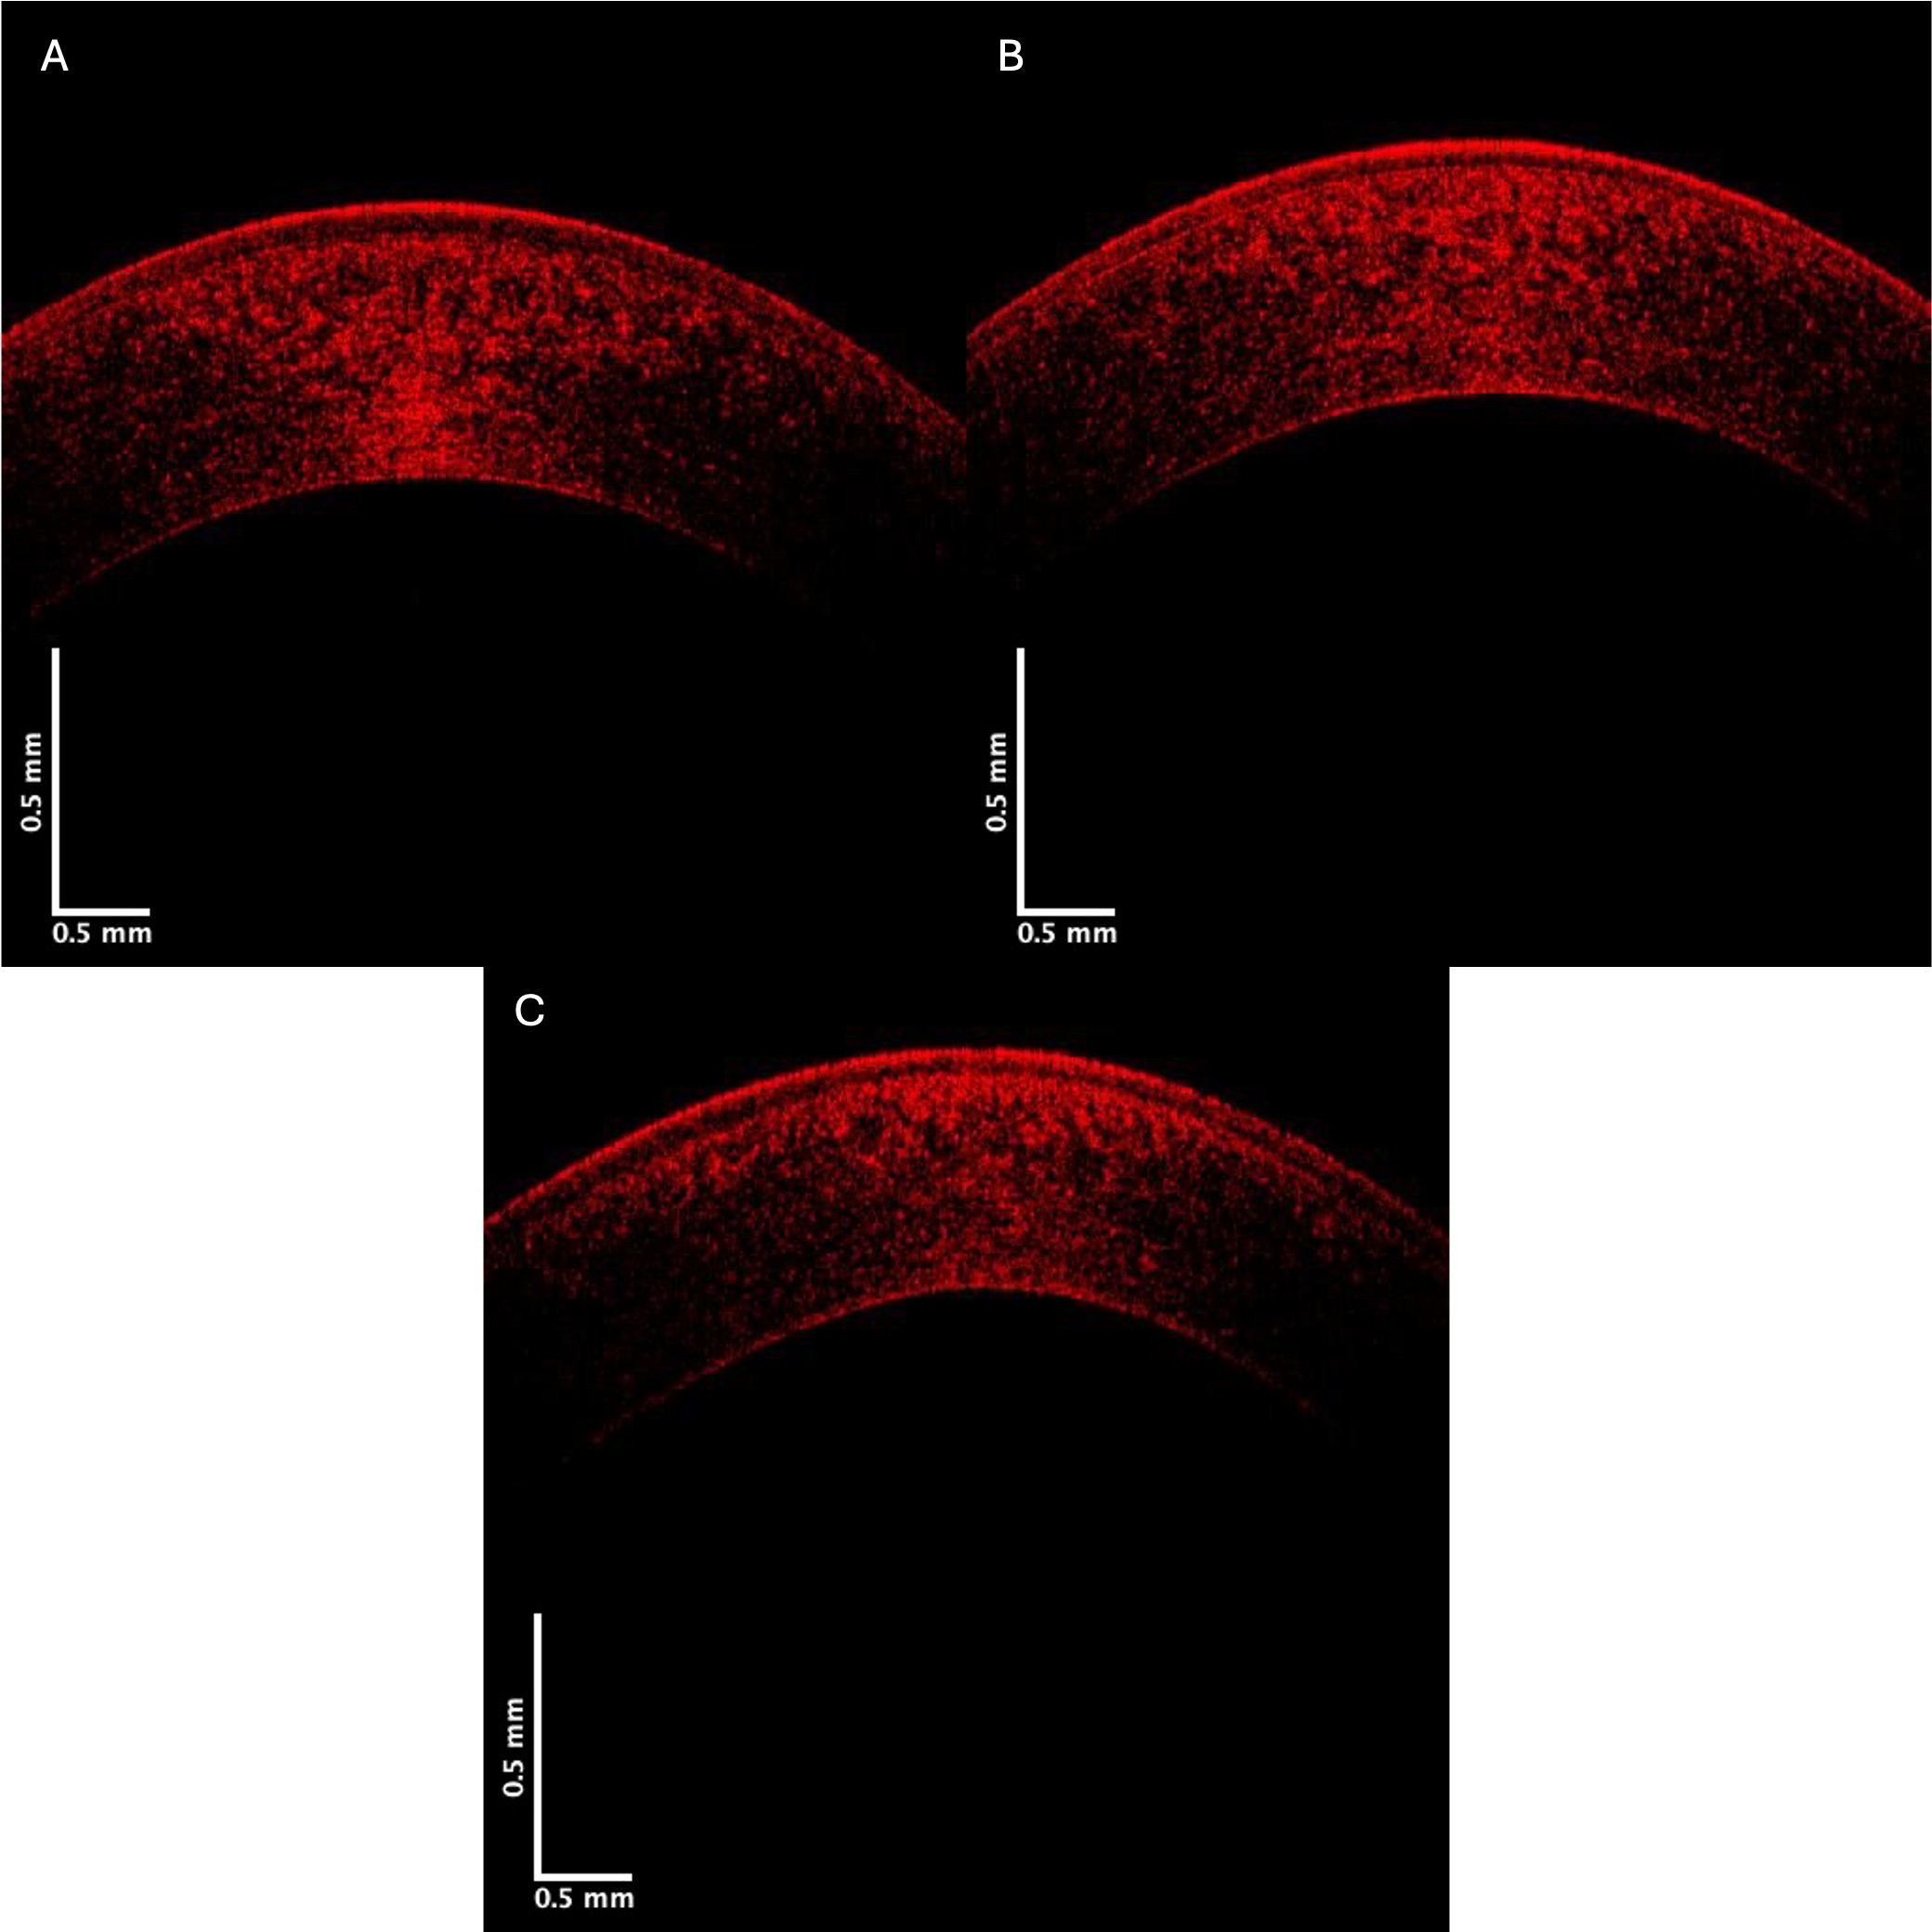

The control and KC cornea images were compared when the grayscale images of the control and KC corneas were separated into individual low (green), medium (blue), and high (red) pixel intensities. Fig. 3 shows the OCT images of the central cornea green channel in typical control (A), Stage II (B), and Stage IV (C) KC corneas. Note the decreased green channel pixel intensity in the posterior central cornea compared to the control and Stages III and IV corneas (Fig. 3).

Fig. 3. Typical green central cornea subchannel images of control (A), Stage II (B), and Stage IV (C) KC corneas. Note the apparent decreased pixel intensity in the posterior region of the corneas in Stages II and IV KC, which suggests a loss of cells (keratocytes) in the posterior cornea.

Pixel intensity versus depth plots for the green channel are shown in Fig. 4. Previous studies on skin demonstrated that the green channel represents the low-intensity cellular contribution to the reflected light [12]. The images in Fig. 4 show that the decreased cellular contribution, presumably of the keratocytes, to the green image decreases in KC.